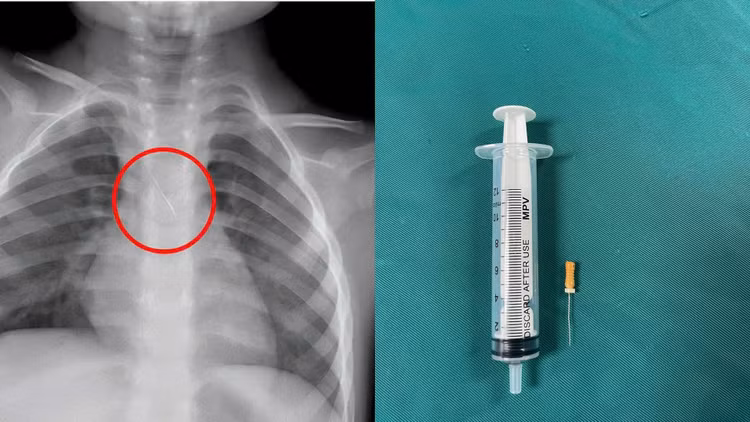

Trước đó, bệnh nhi N.Q.T.Đ. (3 tuổi, trú tại xã Cửa Việt) nhập viện trong tình trạng ho nhiều, ho sặc. Kết quả chẩn đoán hình ảnh cho thấy, bệnh nhi bị sặc kim chọc tủy vào đường thở.

Qua thăm khám và chụp phim, các bác sĩ xác định bé bị sặc kim chọc tủy dài khoảng 22mm, vị trí mắc tại góc carina, nơi chia đôi khí quản.

Dị vật này dài khoảng 22mm, nằm ở góc carina (nơi vùng chia đôi khí quản), một đầu nhọn cắm vào 1/3 dưới khí quản, một đầu tròn nằm trong phế quản gốc trái.

Dị vật trong đường thở của bệnh nhi. Ảnh BV